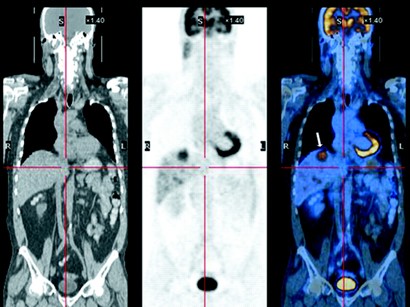

PET / CT görüntüleme tekniğinin bilhassa kanser hastalıklarında kanser vakalarında erken teşhis ve tanı koyma aşamasında oldukça büyük bir önem arz etmektedir. PET / CT görüntüleme tekniği özellikle akciğer kanseri hastalıklarında erken tanı sağlayabilmek adına çok sık olarak kullanılmakta ve faydası fazlası ile görülmektedir. PET / CT görüntüleme sistemi sayesinde erken teşhis sağlanabilen hastalıklardan bazılarını sıralayacak olursak; Malign , Melanoma , lenfome , özefagıs ve mide tümörleri , primer kemik tümörleri , baş tümörleri , boyun tümörleri ve buna benzer bir çok tümör hatalığının erken tanı sağlamaktadır. Kanser vakaları olarak ta meme kanseri , jinokolik hastalıklar yani kadın hastalıkları , kadın kanserleri , kolorektal kanserler , deri kanserleri , kolon kanserleri gibi bir çok kanserde de etkin bir şekilde kullanılarak fayda sağlanmaktadır. Hatta daha önceden tespit edilmiş tümörleşmiş kanser hücrelerinin iyi huylumu kötü huylumu olduğunu tespit etmekte de kullanılmaktadır.